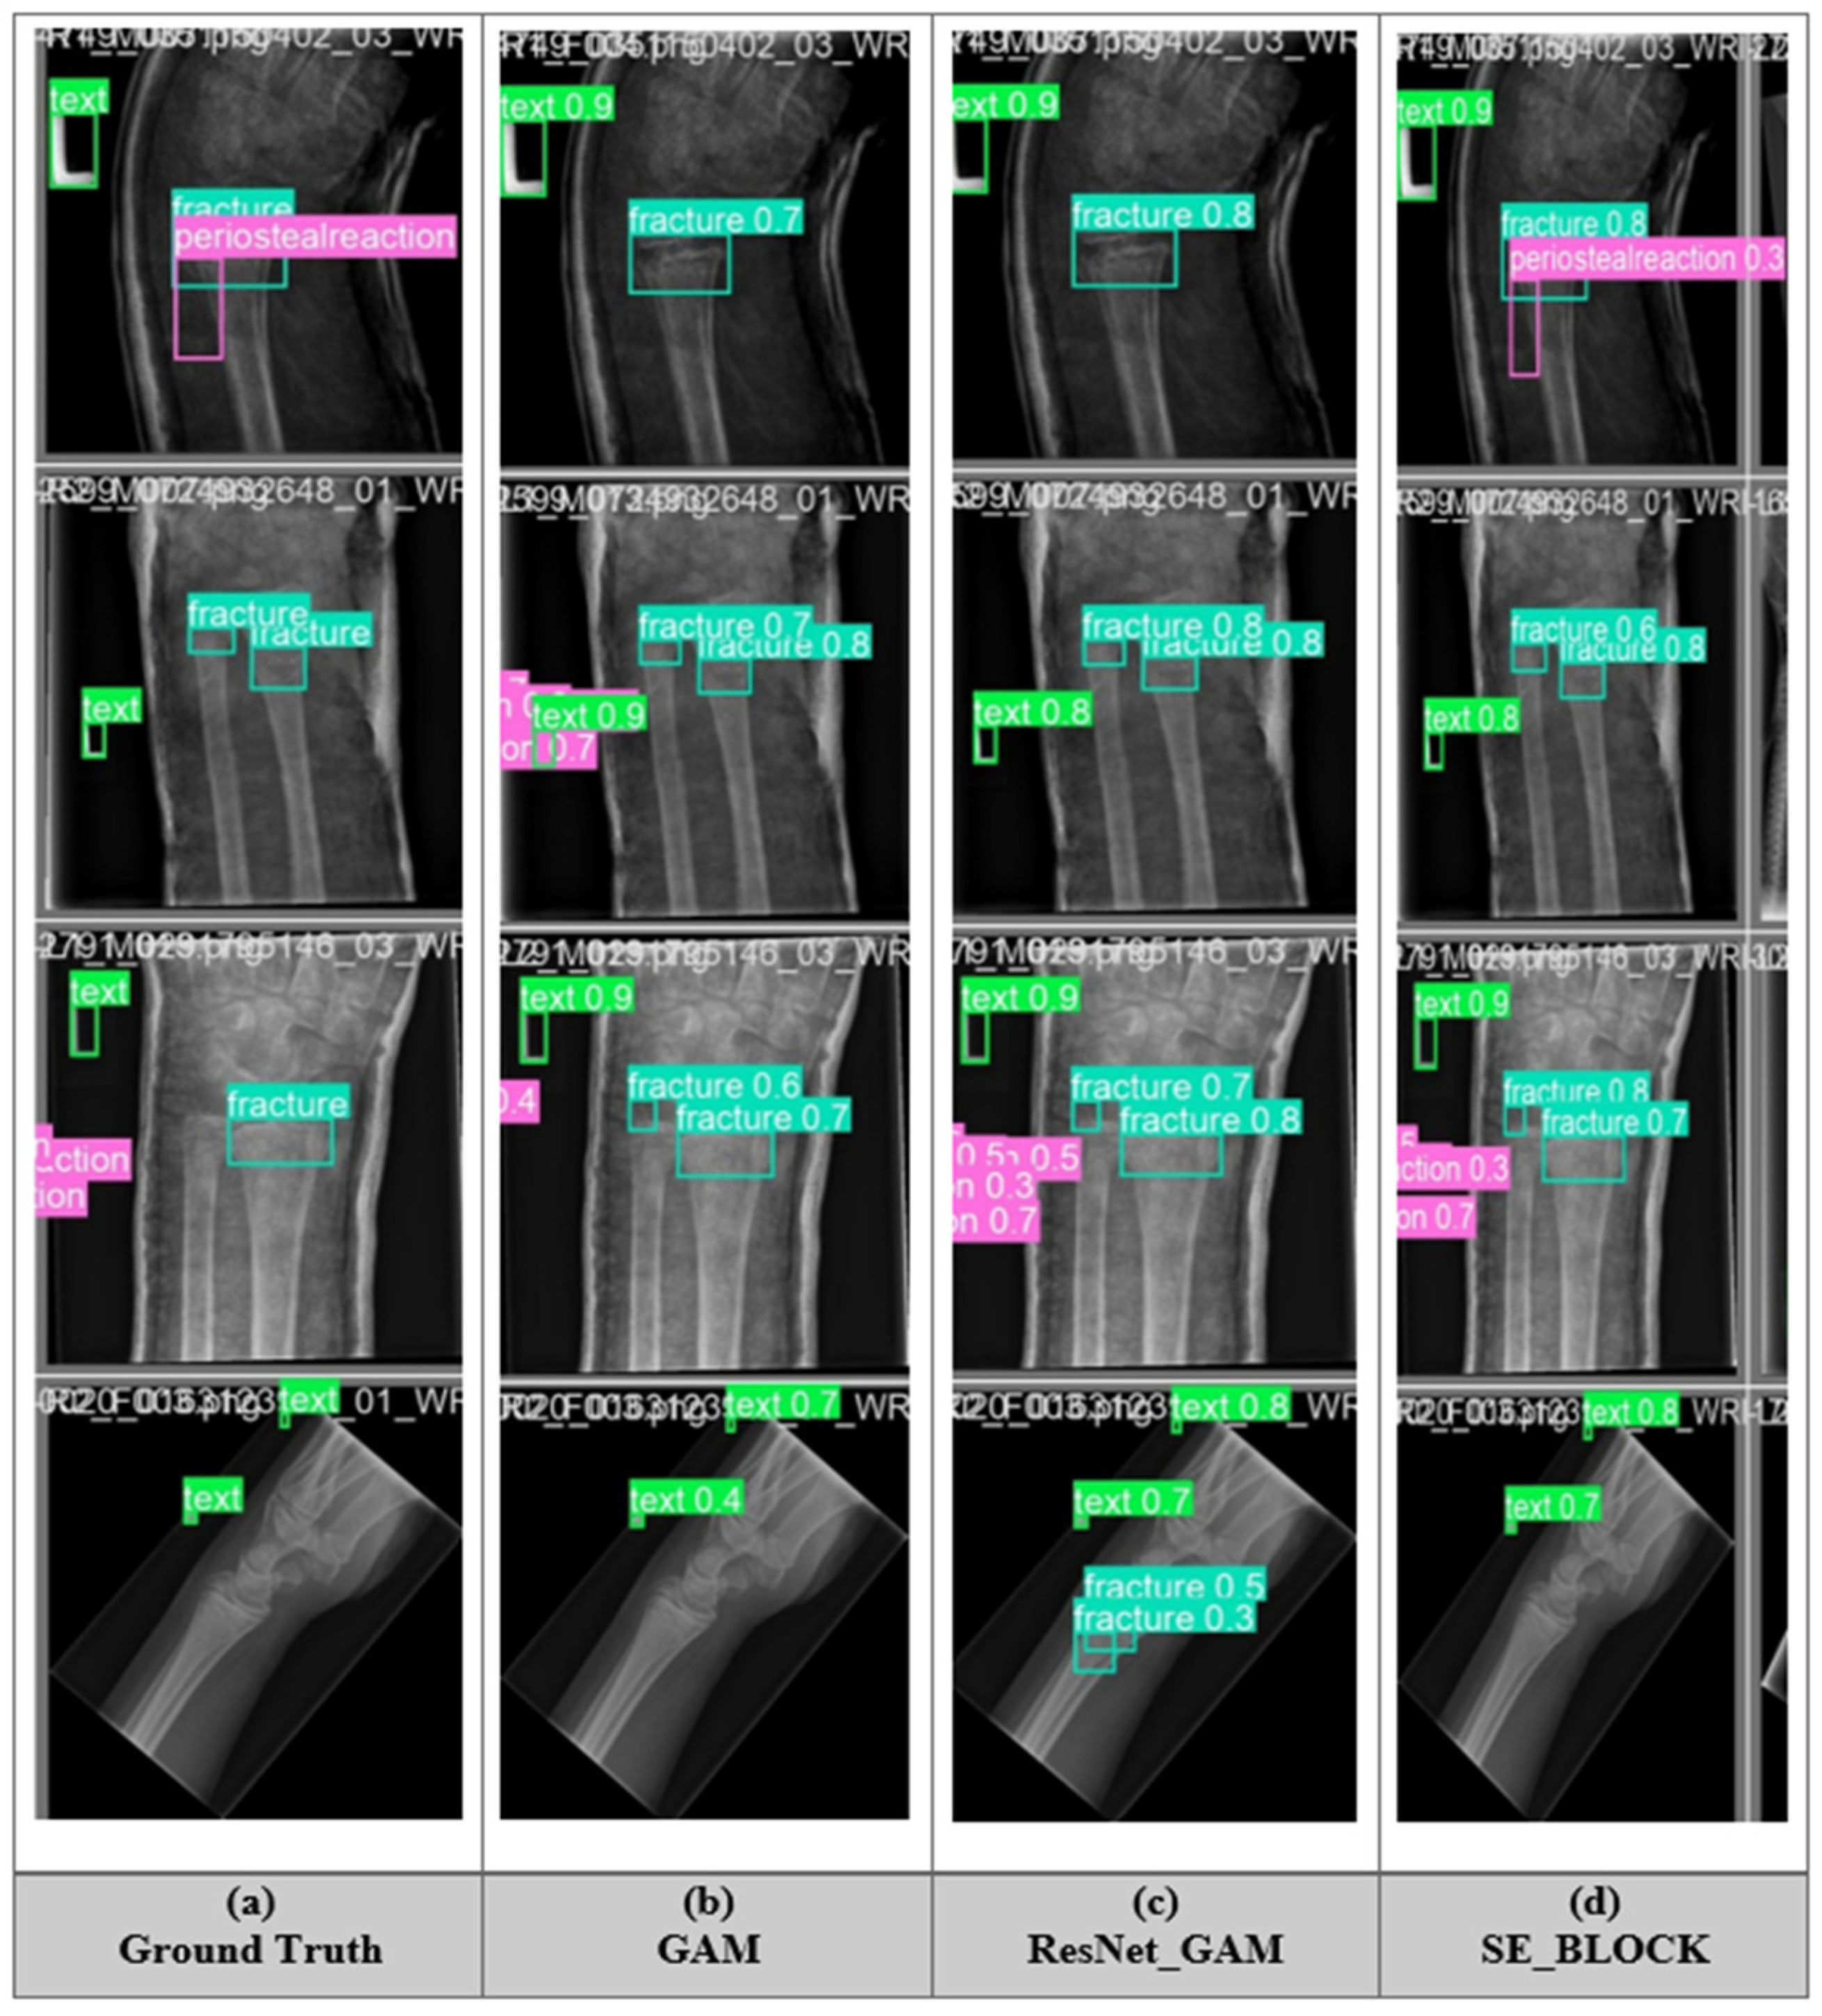

5.5. Fracture Detection of All Model

The fracture detection performance of different YOLO11 models was improved with attention mechanisms. The first column represents the Ground Truth (GT), showing the actual fractures and text annotations, while the following three columns display predictions from different attention-refined YOLO11 models: GAM (i.e., Global Attention Mechanism), ResNet_GAM (i.e., Residual Global Attention Mechanism), and SE_BLOCK (i.e., Squeeze-and-Excitation Block), displayed below in Figure 6. The bounding boxes indicate detected fractures (i.e., cyan), text regions (i.e., green), and Periosteal reactions (i.e., magenta), each with confidence scores. From the comparison, it is evident that the models vary in their ability to detect fractures accurately. The SE_BLOCK model appears to detect more fractures with higher confidence scores, suggesting that it captures fine details effectively. GAM and ResNet_GAM models offer balanced detections, identifying fractures with reasonable confidence but sometimes missing smaller or less distinct ones. The GT box serves as a benchmark, highlighting the actual fracture locations, against which the model predictions can be evaluated. The image demonstrates the role of attention mechanisms in enhancing the diagnostic accuracy of YOLO11 with ResNet_GAM for medical imaging applications. The ResNet_GAM model, functioning as a CAD tool, assists radiologists in detecting fractures, improving the efficiency and reliability of diagnoses. This graphical analysis additionally confirms that attention-based modules not only help in locating fractures but also decrease false positives in non-fracture regions. The better-quality localization and confidence scores, particularly with SE_BLOCK, highlight the effectiveness of channel-wise recalibration. Such improvements are vital in clinical scenarios, where accurate interpretation of subtle signs in X-rays is essential for early diagnosis and timely treatment planning. Moreover, integrating attention into lightweight detection frameworks ensures faster inference with high sensitivity, which is helpful for point-of-care and real-time analysis.

Figure 6.

Examples of results of different YOLO11 models applied to pediatric wrist fracture detection and Ground-Truth: (a) Manually labelled data; (b) GAM (c) ResNet_GAM (d) SE_BLOCK.